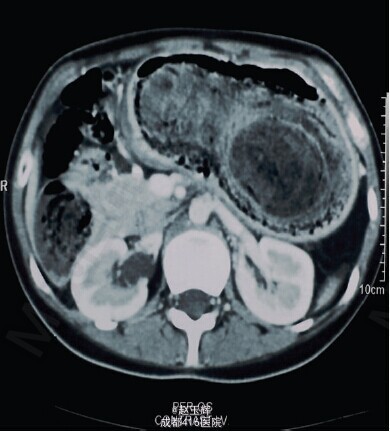

15 岁女性,从 5 岁开始有吞食自己头发的习惯,最近 2 个月出现食欲减退和中度体重减轻就诊;患者有间断性腹部疼痛和餐后呕吐加重,入院常规检查发现贫血,腹部触及上腹部到脐周的质硬肿物和肠鸣音亢进。超声提示胃内的巨大异物,CT 提示胃内的巨大低密度、不均质影,呈网状,胃镜证实异物为毛发结石。 遂行剖腹手术,在膨胀的胃前壁纵行切开,取出异物。术中见胃石突出延伸到近端十二指肠和约 1cm 的空肠。毛发胃石重 1023g,大小约 25cm×11cm×6cm。 取出胃石后,发现幽门前壁溃疡。缝合胃壁后行胃镜检查,确认胃石的完整移除和有无其他异常。术后第 5 天 CT 正常,无并发症,随后出院并建议精神科治疗。 拉庞泽尔氏综合征(Rapunzel Syndrome) 1986 年由 Vaughan Jr 等首先描述:拔毛癖患者形成的毛发胃石进入小肠。通常表现为腹痛、呕吐、恶心、营养不良、吐血、腹泻、便秘。此疾病通常表现为胃的呕吐或者吸收障碍相关的症状。据 Naik 等的研究称症状最多见的为腹痛(37%),恶心呕吐(25.9%),腹膜炎(7.4%),厌食、呕血、肠套叠(7.4%);治疗包括腹腔镜或剖腹探查取出结石,剖腹探查的术式因成功率高、并发症少等成为首选,为了减少复发,患者应该在手术后接受精神科治疗及长期随访。Athanasiou A, Michalinos A,et al.Case Rep Med. 2014;2014:267319. Epub 2014 Nov 6.全文链接:http://www.hindawi.com/journals/crim/2014/267319/